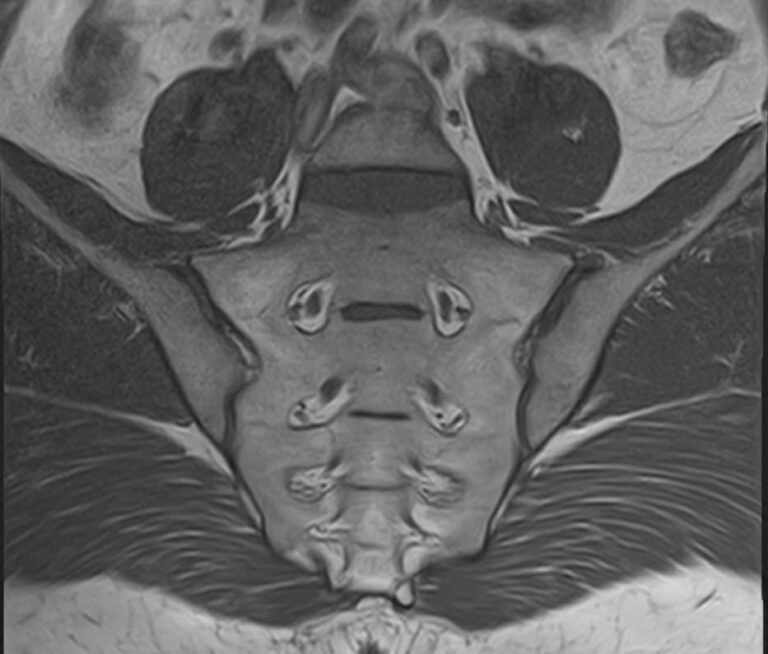

Наиболее точным и эффективным способом диагностики причин появления болей в нижней части спины является МРТ. С помощью данного метода можно оценить состояние всех анатомических структур позвоночного столба на исследуемом уровне, диагностировать поражение позвоночника на начальной стадии, когда другие методы не дают результатов. Такой патологией, в частности, является сакроилеит (воспаление крестцово-подвздошного сочленения), который часто становится причиной анкилоза (сращения) или нестабильности (патологической подвижности) сустава. Выявление сакроилеита на ранней стадии значительно улучшает прогноз в плане лечения и профилактики осложнений.

В клинике «Доступная медицина» диагностика патологии нижней части спины осуществляется на высокотехнологичном оборудовании – новейшем высокопольном томографе TOSHIBA VANTAGE TITAN 1,5 Тесла, который обеспечивает высочайшее качество изображений, точность и достоверность полученных данных. Магнитно-резонансная томография осуществляется без применения ионизирующего излучения, поэтому является безопасным методом обследования и может применяться неоднократно по мере необходимости.

Что можно диагностировать при проведении МРТ пояснично-крестцового отдела позвоночника + МРТ крестцово-подвздошных сочленений

При проведении данного комплексного обследования можно выявить:

• дегенеративно-дистрофические заболевания позвоночника: спондилез, спондилоартроз, остеохондроз;

• стеноз (сужение) позвоночного канала;

• грыжи межпозвонковых дисков (протрузии, экструзии);

• переломы позвонков, их смещение;

• спондилиты, гнойные артриты, сакроилеит, абсцессы околопозвоночных тканей и другие воспалительные заболевания, туберкулез;

• опухоли позвоночника и окружающих тканей;

• патологические изгибы позвоночника, сколиоз, усиленный или выпрямленный лордоз как нарушение статической функции позвоночника;

• аномалии строении позвоночника.